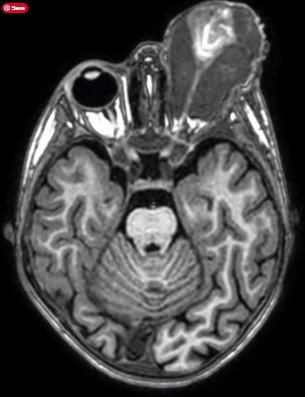

روى مدير عام مركز الحسين للسرطان الدكتور عاصم منصور حالة لطفل غزاوي مصاب بورم في العين، الذي التهم كامل عينه وانطلق خارجها. بحسب وصفه. وأوضح منصور أن نسبة الشفاء من هذا النوع مرتفعة لو تم نقل الطفل مبكرا دون عرقلات الاحتلال. وبين منصور أن معظم الأطفال الذين وصلونا من هناك كانوا في حالة متقدمة من المرض. وتاليا ما كتبه الدكتور منصور عبر حسابه على فيس بوك: “صورة الرنين المغناطيسي هذه لطفل غزيّ مصاب بورم في العين، ولا تحتاج أن تكون طبيباً مختصاً في علم الأشعة أو طب العيون لتدرك حجم الورم الذي التهم كامل العين لا بل انطلق خارجها. لو تم نقل هذا الطفل مبكراً لتمكنا من انقاذ هذه العين، فنسبة الشفاء من هذا النوع من الأورام مرتفعة جداً، لكن الاحتلال عرقل خروجه كما هو حال آلاف المرضى، ليصلنا بهذه الحالة المتقدمة جداً. معظم الأطفال الذين وصلونا من هناك كانوا في حالة متقدمة من المرض. أعلم أن هذه الحالات قد لا تسترعي الانتباه في ظل الكارثة الإنسانية وحجم المحرقة المستمرة منذ أكثر من عام لكن لا بد لنا من وقفة جادة لإنقاذ حياة الاف مرضى السرطان الذين يعانون بصمت ولا يجدون أبسط مقومات العلاج”.